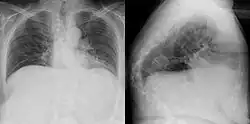

Gibbus deformity in a chest X-ray (frontal and lateral) of an old woman.

Gibbus deformity is a form of structural kyphosis typically found in the upper lumbar and lower thoracic vertebrae, where one or more adjacent vertebrae become wedged. Gibbus deformity most often develops in young children as a result of spinal tuberculosis and is the result of collapse of vertebral bodies.[1][2][3] This can in turn lead to spinal cord compression causing paraplegia.[4][5]

Gibbus deformity is included in a subset of structural kyphosis that is distinguished by a higher-degree angle in the spinal curve that is specific to these forms of kyphosis. Other conditions within this subset include Pott's disease and Scheuermann kyphosis, but gibbus deformity is marked by an especially sharp angle. Viewed from behind, the resulting hunchback is more easily seen when bending forward.[10] A kyphosis of >70° can be an indication of the need for surgery and these surgeries can be necessary for children as young as two years old, with a reported average of 8 years of age.[9]